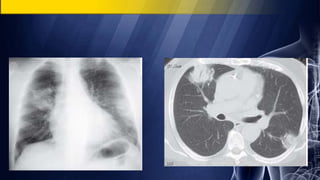

Lung Cancer

Lung cavity in edentulous patient more likely from

cancer than abscess

Thickest portion of cavity wall > 15 mm suggests tumor

Nodular cavity wall

Less likely to exhibit surrounding consolidation